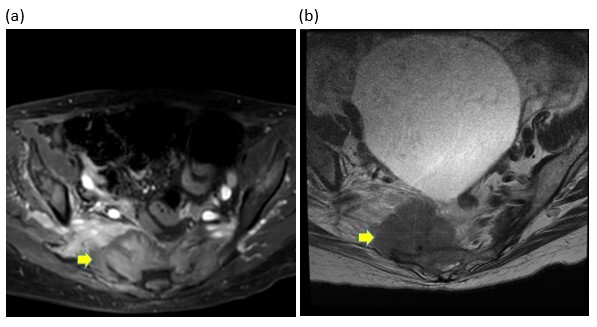

On admission, blood counts and serum chemistries were unremarkable except for mild anemia. Erythrocyte sedimentation rate (ESR) and C-reactive protein (CRP) levels were elevated at 84 mm/hour and 18.1 mg/dL respectively. Urinalysis and culture ruled out urinary tract infection as a cause for retention and overflow incontinence. Urgent magnetic resonance imaging (MRI) of the whole spine with contrast revealed multifocal areas of marrow replacement in the sacrum and adjacent bilateral iliac bones with a soft tissue mass centered at the right sacral ala infiltrating the right sacral neural foramina (S2-S4) causing cauda equina compression, and marrow replacement of L3, L4, and L5 vertebral bodies (Figure 1). There were additional lesions in the cervical and thoracic spine without spinal cord compression. These multifocal spine lesions were highly suggestive of metastatic cancer. Computed tomography (CT) of the chest, abdomen and pelvis with intravenous contrast revealed multiple bilateral pulmonary metastases. Whole-body Tc-99-MDP scan revealed extensive bony metastases involving the left proximal femur and left distal tibia in addition to the known lesions described.